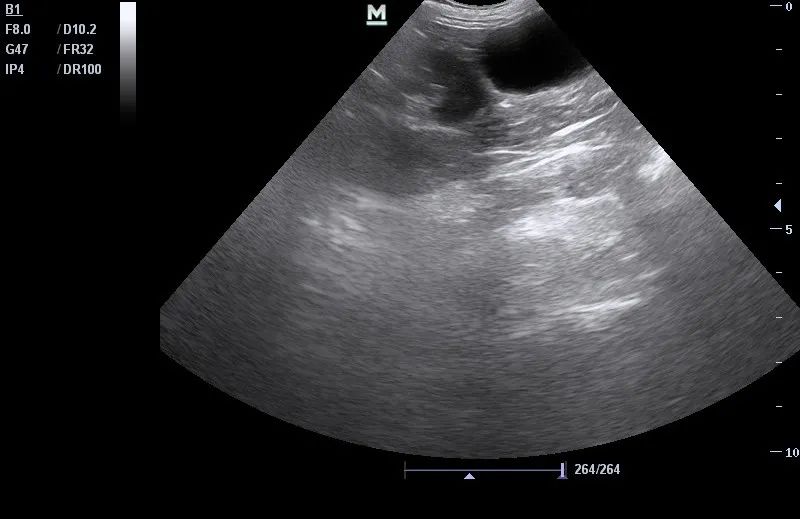

B超检查

猫糖尿病、子宫蓄脓感染

患猫需要控制好血糖的后,做子宫病理性摘除术,术后对伤口护理,并控制好血糖 ,术后第六天,血糖控制良好,伤口愈合良好。